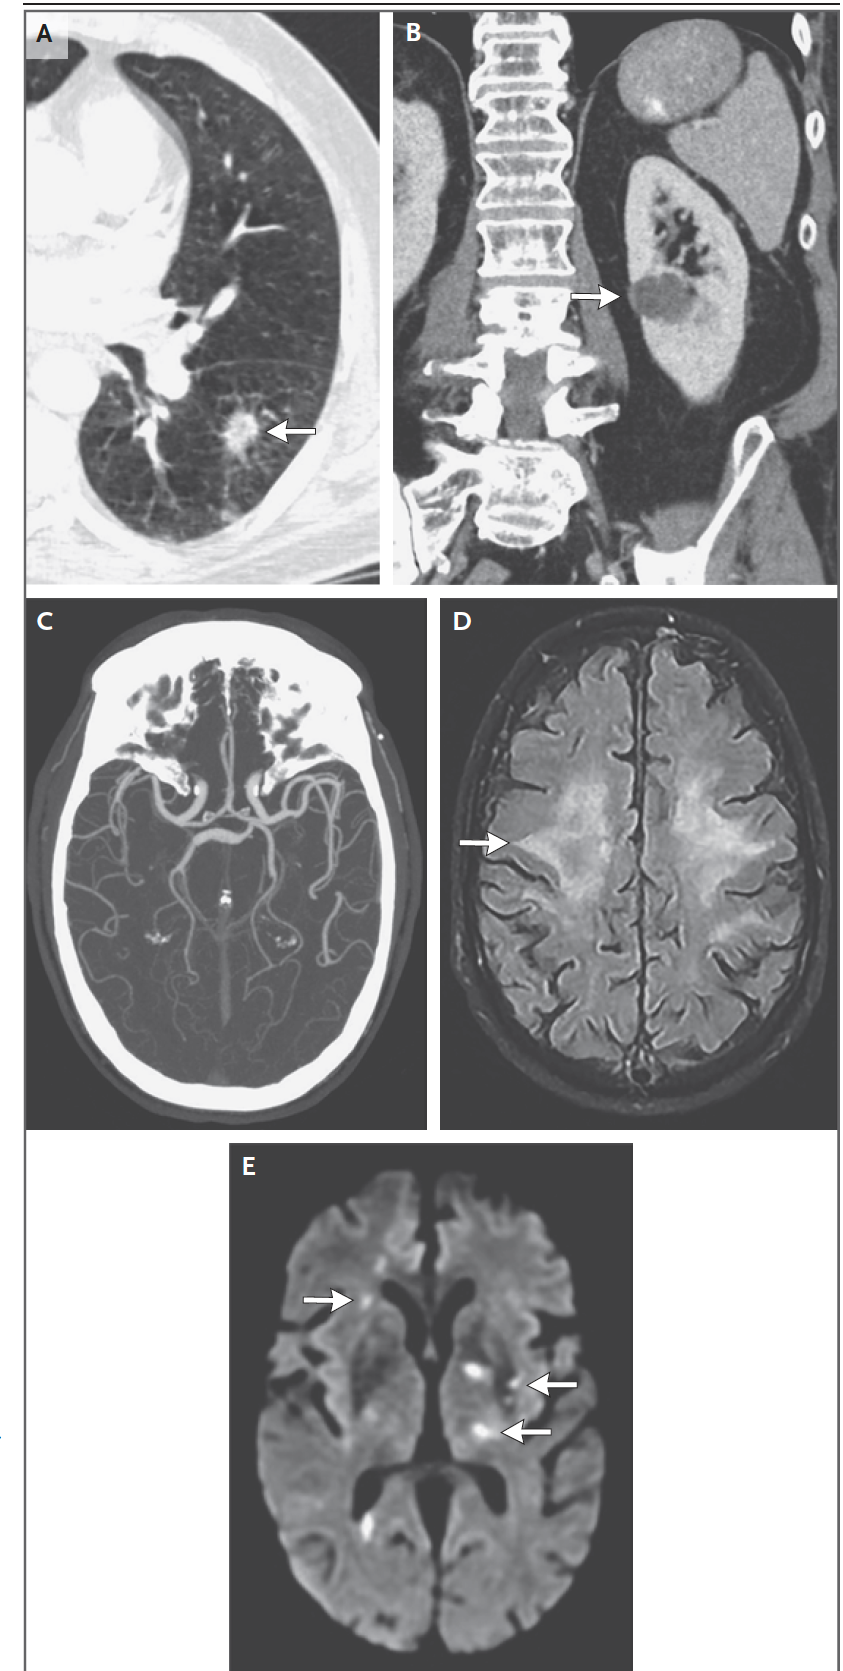

下图1. 胸部CT(图1A)左肺下叶可见一占位(直径1.7 cm)(箭头),病灶周围线样信号。腹部CT(图1B)显示左肾前皮质一个外生性低密度肿块(直径1.6cm)

本院头颈CTA(图1C),显示左额放射冠和右大脑脚内的局灶性脑软化。动脉粥样硬化改变导致颈动脉和颅内动脉多灶轻度狭窄。平扫头部MRI(图1D和1E)显示多发新急性梗死小病灶,包括双侧半卵圆中心和放射状冠、左侧丘脑、左侧内囊和豆状核、左侧岛叶下区、右中央前回内侧、右前额叶、额叶上回和右颞叶。在Flair和T2加权成像中,可见脑室周围和皮层下白质几个分散斑片状高信号,这些发现提示存在中度小血管疾病。患者住院后,静脉注射肝素。第二天经胸超声心动图显示射血分数正常,无瓣膜赘生物或卵圆孔未闭。血液培养显示没有细菌生长。